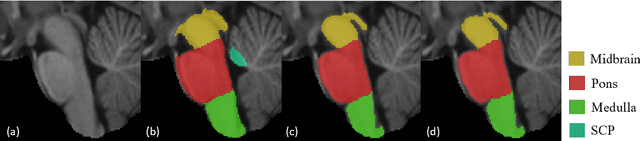

About 5-8% of individuals over the age of 60 have dementia. With our ever-aging population this number is likely to increase, making dementia one of the most important threats to public health in the 21st century. Given the phenotypic overlap of individual dementias the diagnosis of dementia is a major clinical challenge, even with current gold standard diagnostic approaches. However, it has been shown that certain dementias show specific structural characteristics in the brain. Progressive supranuclear palsy (PSP) and multiple system atrophy (MSA) are prototypical examples of this phenomenon, as they often present with characteristic brainstem atrophy. More detailed characterization of brain atrophy due to individual diseases is urgently required to select biomarkers and therapeutic targets that are meaningful to each disease. Here we present a joint multi-atlas-segmentation and deep-learning-based segmentation method for fast and robust parcellation of the brainstem into its four sub-structures, i.e., the midbrain, pons, medulla, and superior cerebellar peduncles (SCP), that in turn can provide detailed volumetric information on the brainstem sub-structures affected in PSP and MSA. The method may also benefit other neurodegenerative diseases, such as Parkinson's disease; a condition which is often considered in the differential diagnosis of PSP and MSA. Comparison with state-of-the-art labeling techniques evaluated on ground truth manual segmentations demonstrate that our method is significantly faster than prior methods as well as showing improvement in labeling the brainstem indicating that this strategy may be a viable option to provide a better characterization of the brainstem atrophy seen in PSP and MSA.